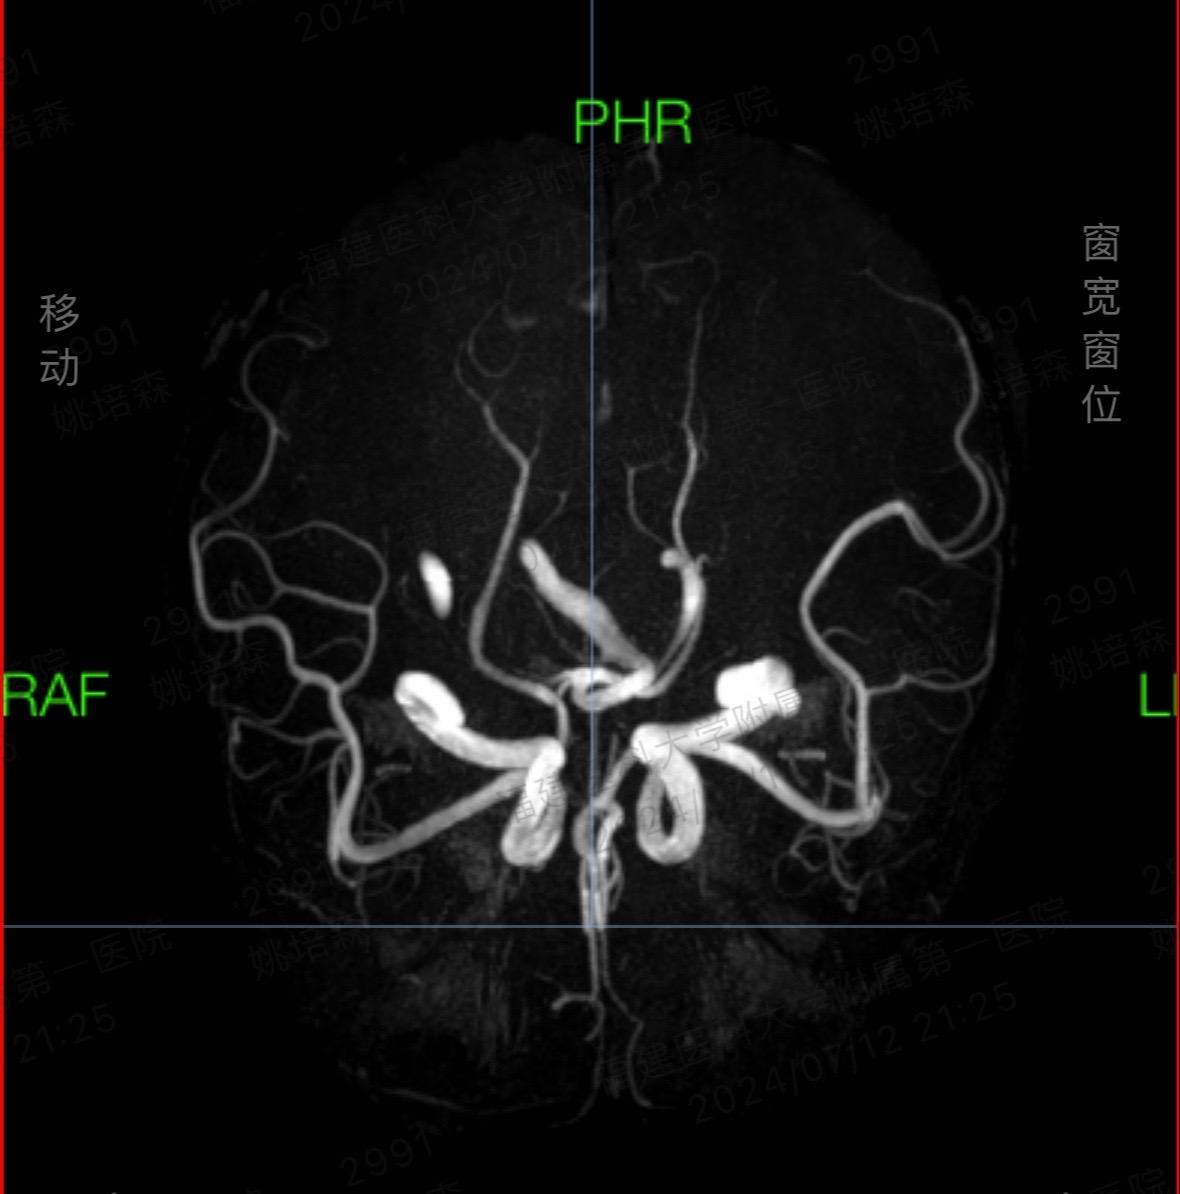

时光晃呀晃。连续10小时颅脑手术室日常 微创手术 手术,做了一台帕金森病,一台面肌痉挛,一台三叉神经痛,一台脑膜瘤,时光把我一整天晃走了,还让我累成了某某某!